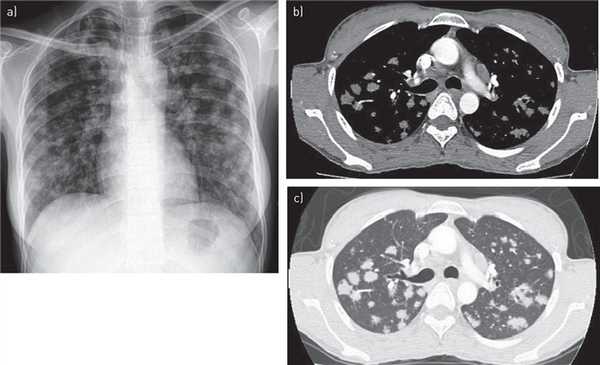

(Слева) На аксиальном срезе при КТ с контрастным усилением у молодой женщины, больной СПИДом, выявлена брыжеечная и забрюшинная лимфаденопатия. В некоторых из увеличенных лимфоузлов видны центральные некротические казеозные массы низкой плотности характерные для микобактериальной инфекции.

(Справа) На аксиальном КТ срезе определяется большое кистозное объемное образование в воротах печени и в области головки поджелудочной железы — конгломерат увеличенных лимфоузлов с изменениями по типу казеозного некроза в результате микобактериальной инфекции (М. tuberculosis). (Слева) На аксиальном КТ срезе визуализируется полость и распространенные (в нескольких долях) изменения по типу бронхоальвеолярной инфекции легких, типичные для активной формы туберкулеза. Эта пациентка — молодая женщина, студентка из Азии, приехавшая на учебу «по обмену».

(Справа) На аксиальном срезе у этой же пациентки определяется утолщение стенки слепой кишки в сочетании с регионарной брыжеечной лимфаденопатией, что типично для кишечной и внутриузловой локализации ТБ. (Слева) На аксиальном КТ срезе видно уменьшенную в размерах, нефункционирующую и частично обызвествленную почку (нефрокальциноз) - типичное проявление хронической туберкулезной почечной инфекции. У пациента в анамнезе имеется туберкулез легких.

(Справа) При аксиальной КТ выявлены обызвествленные в результате успешного противотуберкулезного лечения гранулемы в забрюшинных и позадиножковых лимфоузлах. Левая почка тотально обызвествлена и нефункциональна, аутонефрэктомия произошла вследствие хронического туберкулеза почки. Мелкие фокальные обызвествления также имеют место и в надпочечниках.